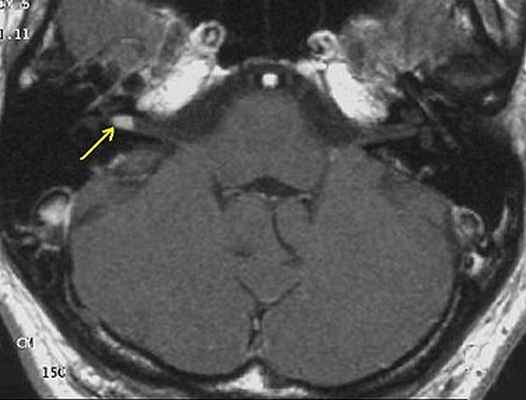

На МРТ выявляется ровный контур опухоли и по её периферии полоска сигнала так называемой «ликворной щели», деформация мозжечка и ствола головного мозга. При распространении невриномы во внутренний слуховой проход, внекананальная её часть имеет вид «свисающей капли» [30] .

Приблизительно 2 /3 неврином выглядят гипоинтенсивными, а одна треть изоинтенсивными на Т1-взвешенных томограммах. На Т2-взвешенных томограммах невриномы характеризуются повышением сигнала, степень которого варьирует. Участки гетерогенно изменённого сигнала (вследствие образования кист) характерны для новообразований больших размеров (как правило более 3 см). Все невриномы интенсивно накапливают контрастные вещества, более чем в 70 % случаев их накопление гетерогенно [30] .